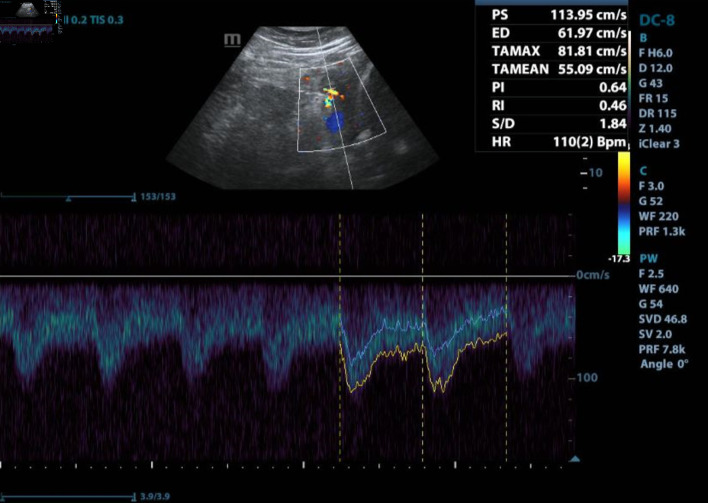

围产期心肌病(PPCM)是孕产妇健康的重大挑战,其特点是在妊娠晚期或产后早期出现射血分数降低的心力衰竭。尽管人们对 PPCM 的认识有所进步,但它仍然威胁着产妇的生命,并导致大量产妇发病和死亡。本文回顾了与 PPCM 相关的流行病学、病因学、诊断难题、管理策略和结果。本文报告了一名 29 岁女性 PPCM 患者的病例,强调了早期识别和针对性治疗的重要性。患者发病时症状不典型,包括排尿困难、腰痛、持续发热和口服不耐受。尽管进行了积极的医疗干预,但患者还是在入院后 48 小时内因心肺骤停而不幸去世。本病例凸显了诊断和管理 PPCM 所面临的挑战,尤其是在出现非特异性症状时,并强调迫切需要改进诊断标准和治疗干预措施,以减轻患者的不良后果。

Peripartum cardiomyopathy (PPCM) poses a significant challenge in maternal health, characterized by heart failure with reduced ejection fraction during late pregnancy or early postpartum. Despite advances in understanding PPCM, it remains life-threatening with substantial maternal morbidity and mortality. This article reviews the epidemiology, etiology, diagnostic challenges, management strategies, and outcomes associated with PPCM. A case report of a 29-year-old woman with PPCM is presented, emphasizing the importance of early recognition and tailored management. The patient's presentation was marked by atypical symptoms, including dysuria, lumbar pain, persistent fever, and oral intake intolerance. Despite aggressive medical intervention, the patient experienced a tragic outcome, succumbing to cardiopulmonary arrest within 48 h of admission. This case underscores the challenges in diagnosing and managing PPCM, particularly when presenting with nonspecific symptoms and emphasizes the urgent need for improved diagnostic criteria and therapeutic interventions to mitigate adverse outcomes in affected individuals.